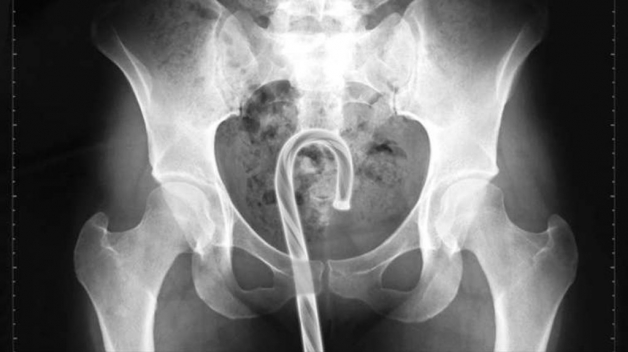

83 neskutečných věcí, které si Američané v roce 2015 strkali do všech možných tělních otvorů Radka Pružinová